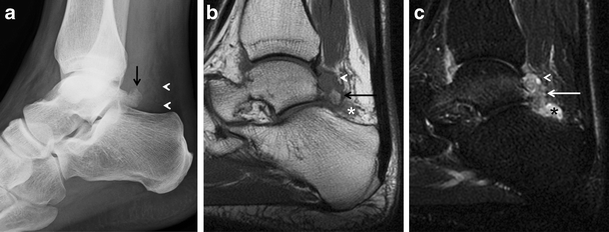

Os trigonum syndrome. a Lateral radiograph of the ankle demonstrates an os trigonum (arrow) and posterior soft-tissue prominence and infiltration of the pre-Achilles fat (arrowheads). Sagittal T1-weighted (b) and STIR (c) MRIs show bone marrow oedema (arrows) in the os trigonum, posterior recess nodularity and thickening (arrowheads), and a joint effusion (asterisk). The patient was a runner with clinical posterior impingement